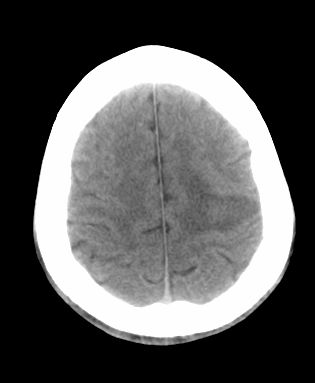

男 42岁 头痛20天

左顶叶见片状低密度影,边界不清,内见斑片状等密度影。考虑转移性肿瘤可能性大,建议ct增强或mr增强扫描。建议胸部检查,排除肺部病变。

左顶叶见片状低密度影,内似见结节状略高密度影,建议增强扫描。

左侧顶叶低密度灶,性质待定;建议行ct增强扫描或mri检查。

胸部ct未见异常。

左顶叶见片状低密度影,边界不清,内见斑片状等密度影。考虑转移性肿瘤可能性大,建议ct增强或mr增强扫描。建议胸部检查,排除肺部周围型腺癌。

左侧顶叶低密度灶,胶质瘤或转移瘤,建议ct增强扫描或mri检查。